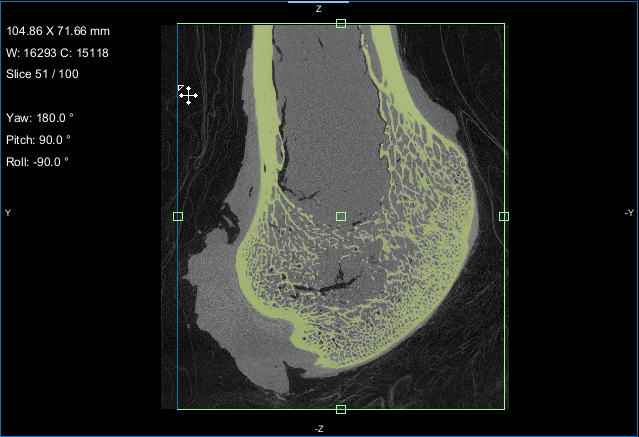

This section of the tutorial describes how to use the Bone Analysis module for 3D volume fraction plotting. You should note that volume fractions are scalar maps.

Comparison of volume fraction scalar map (on left) with vector-based field of anisotropy (on right)

When processing is complete, the volume fraction dataset appears on the Data Properties and Settings panel.

NOTE In most cases, the Jet LUT provides good visualizations of volume fraction.